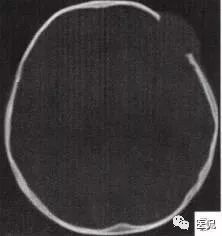

颅脑CT示:图A〜D,CT平扫示左侧额骨、蝶骨见溶骨性骨质缺损,边界清晰,周围无硬化边,伴有软组织肿块向脑外生长,边缘光滑,脑内无明显侵犯;